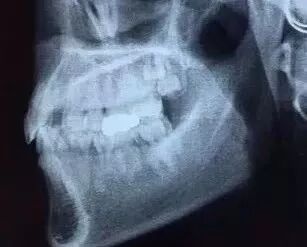

先放几张图,让你们涨涨姿势

不拍片根本不知道

你的牙齿长得会有多“调皮”

全景片曲面断层片

此片意义极大,甚至有时候高于第一张!因为我们可以通过看侧脸来大致判断第一张片子的某些数据,但是如果不拍曲断什么的 ,谁也没办法保证下面有没有肿瘤什么的埋伏牙,囊肿,高钙化骨结节,牙根吸收,根折,甚至恶性肿瘤,医生不拍这个片子,说白了就是给自己埋炸弹,如果看牙过程中发现牙齿出现什么问题,在做之前没发现这些隐患,属于不负责的做法。